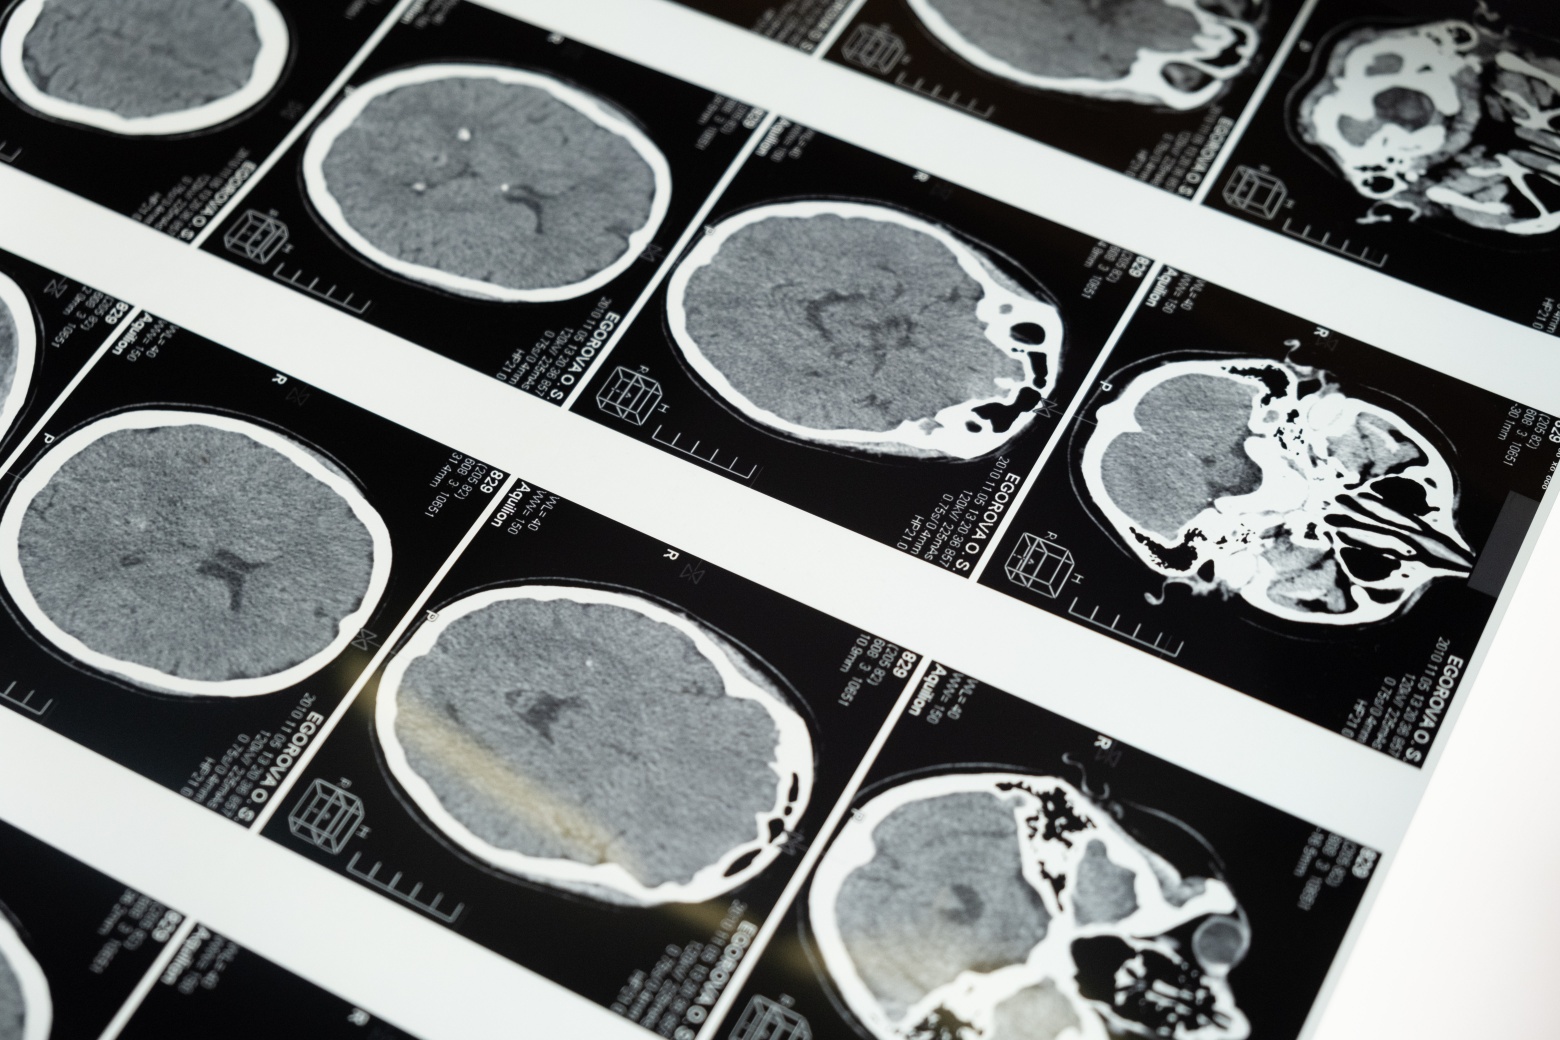

뇌경색은 허혈성과 출혈성으로 나뉩니다.

1. 허혈성 뇌경색

가장 흔한 유형으로 혈전이 혈관을 막아 뇌의 특정 부분으로 혈액과 산소의 흐름을 방해할 때 발생합니다.

허혈성 뇌졸중은 다시 양면성과 혈전성으로 나뉘며 전자는 응혈이 신체에 형성되어 뇌혈관에 응집되었을 때 나타나며 후자는 뇌 속 혈관에 응혈이 생길 때 나타납니다.

2. 출혈성 뇌경색

출혈성 뇌경색은 뇌혈관이 파열되거나 출혈이 발생하여 뇌의 특정 영역으로의 혈류를 차단합니다.

출혈은 뇌 내의 모든 혈관이나 뇌를 둘러싼 막에서 발생할 수 있는데 너무 오랫동안 치료하지 않고 방치하면 뇌경색이 뇌에 영구적인 손상을 일으킬 수 있어서 즉각적인 치료가 필요합니다.